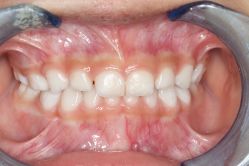

• 青苗儿童口腔(长楹天街购物中心)

• -青苗儿童口腔(长楹天街购物中心)

会员1407914 上传于 20-09-21 | 报错